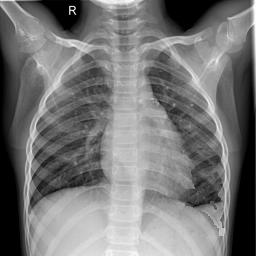

Large numbers of labeled medical images are essential for the accurate detection of anomalies, but manual annotation is labor-intensive and time-consuming. Self-supervised learning (SSL) is a training method to learn data-specific features without manual annotation. Several SSL-based models have been employed in medical image anomaly detection. These SSL methods effectively learn representations in several field-specific images, such as natural and industrial product images. However, owing to the requirement of medical expertise, typical SSL-based models are inefficient in medical image anomaly detection. We present an SSL-based model that enables anatomical structure-based unsupervised anomaly detection (UAD). The model employs the anatomy-aware pasting (AnatPaste) augmentation tool. AnatPaste employs a threshold-based lung segmentation pretext task to create anomalies in normal chest radiographs, which are used for model pretraining. These anomalies are similar to real anomalies and help the model recognize them. We evaluate our model on three opensource chest radiograph datasets. Our model exhibit area under curves (AUC) of 92.1%, 78.7%, and 81.9%, which are the highest among existing UAD models. This is the first SSL model to employ anatomical information as a pretext task. AnatPaste can be applied in various deep learning models and downstream tasks. It can be employed for other modalities by fixing appropriate segmentation. Our code is publicly available at: https://github.com/jun-sato/AnatPaste.